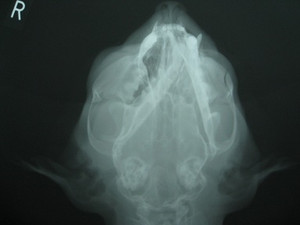

由于猫咪下巴脱臼的表现和其他口腔疾病的表现有相似之处,不好直接判断的铲屎官可以带猫咪去附近医院拍X光片,让医生帮助判断下巴脱臼是否严重。